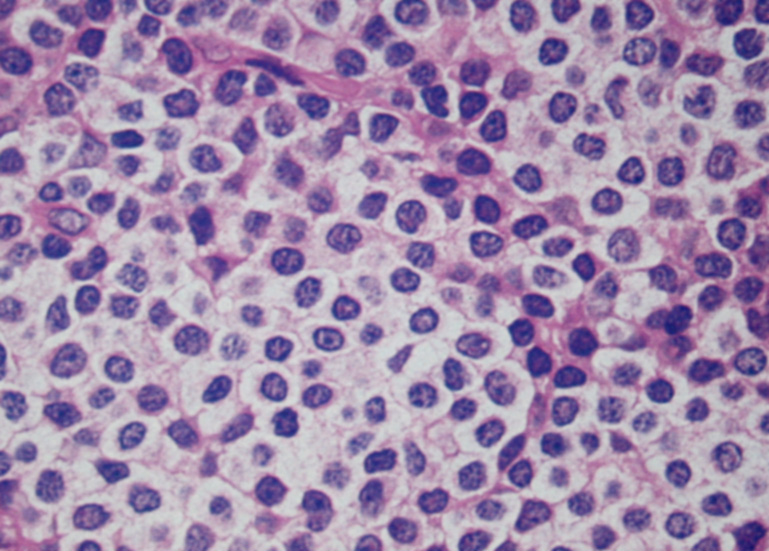

- 典型例はmarginal zoneのcentrocyte-like cellの増殖といわれるが非典型例も多い

| centrocyte-like cell | monocytoid cell | plasmacytoid |